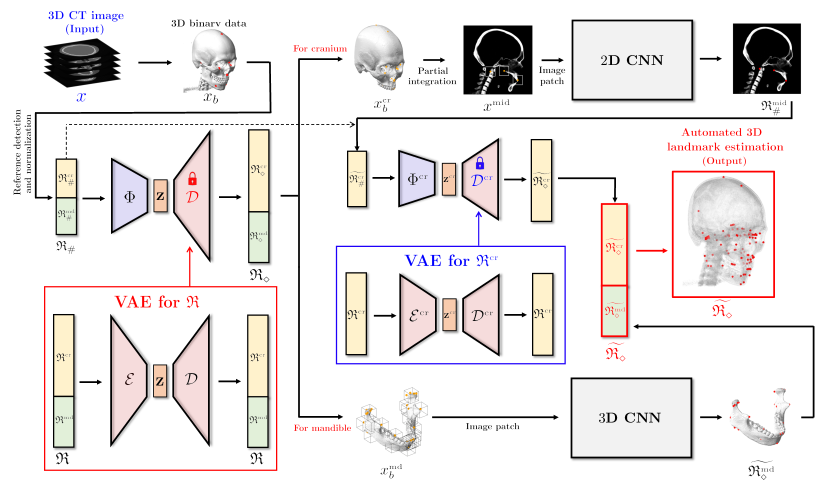

The proposed method attempts to address this problem by taking advantage of a semi-supervised learning framework that permits the utilization of the number of anonymized landmark data whose corresponding CT data are not provided. As shown in Figure 1, the proposed method comprises the following three main steps: (i) To obtain easy-to-find reference landmarks , we apply CNN with 2D illuminated images generated from a binarized CT image and normalize the output with respect to the cranial volume. (ii) A rough estimation of entire landmarks is obtained using the partial knowledge and a VAE-based low dimensional representation of . (iii) Using this estimation, coarse-to-fine detection for is conducted, wherein separate strategies are utilized for the mandibular and cranial landmarks. For the mandibular landmarks, the landmarks are accurately identified by applying 3D patch-based CNNs to capture the morphological features on a 3D surface geometry associated with the landmarks, wherein an input patch is extracted based on the coarse estimation. For cranial landmarks, we first detect three landmarks lying on the midsagittal plane by applying a 2D CNN whose input is an extracted 2D patch from a partially integrated image in basis of the coarse estimation. By utilizing the three finely-detected landmarks and cranial reference landmarks as the partial information of , the remaining cranial landmarks are finely annotated via a VAE-based local-to-global estimation utilizing the same method in the previous step .

The first step of the proposed method is to find 10 reference landmarks from a given . Initially, a CT image is converted into a binarized image by (1). From , 2D illuminated images are generated by manipulating various lighting and viewing directions (see Figure 2). By applying VGGNet [Simonyan2014] to these illuminated images, the reference landmarks are accurately and automatically identified. This detection method is based on that presented in the recent study [Lee2019].

In the binarized image , we separate the mandible from cranium. Kindly refer to the paper [Jang2020] for the segmentation method. Let and denote the separated cranial and mandibular images (as shown in Figure 1). Using these images and the rough estimation , the following fine detection processes are conducted.